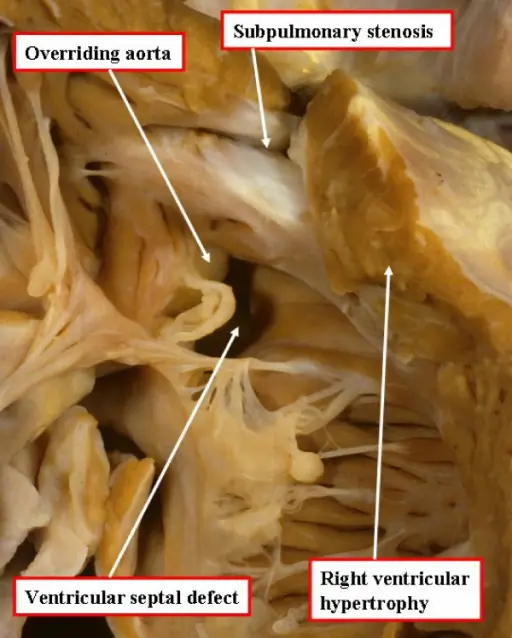

Tetralogy of Fallot (ToF)

Tetralogy of Fallot (ToF) is a congenital cardiovascular anomaly that includes:

- Right ventricular outflow tract stenosis

- Right ventricular hypertrophy

- Ventricular septal defect (VSD)

- An overriding aorta

Early cyanosis is caused by right-to-left shunting, and the degree of stenosis dictates how much shunting and cyanosis is present.